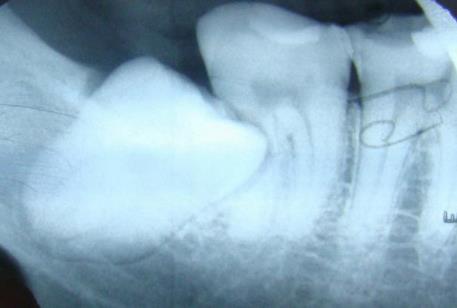

智齿是怎么拔的图解:

智齿一定要拔吗:这种情况智齿一定要拔掉(附拔智齿图)